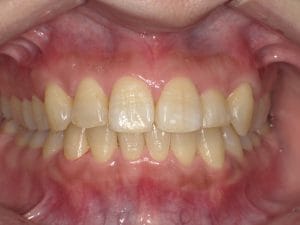

Case028 – セラミック矯正

歯並びと噛み合わせを治したいということを主訴に来院してくださった患者様の症例です。

前医の矯正専門医でマウスピースによる矯正では綺麗にならないといわれ、ワイヤー矯正はしたくなく、当院でセラミックで治したいということで来てくださいました。

初診時カウンセリングを含め計3回の診療、期間は三週間で前歯を内側に引っ込め、噛み合わせが交差咬合という不正咬合になってるところも治しました。

前歯が内側に引っ込むことで、口周りの軟組織もしまってお顔立ちもとても若々しくシュッとされ、より洗練されたイメージになりました。

当院はインビザラインによるマウスピース矯正、ワイヤー矯正、セラミック矯正の全ての矯正をやる事ができますが、その中で患者様のご希望、状態にあったもので、最善の治療をする事を心がけております。

担当 理事長 佐藤 悠野